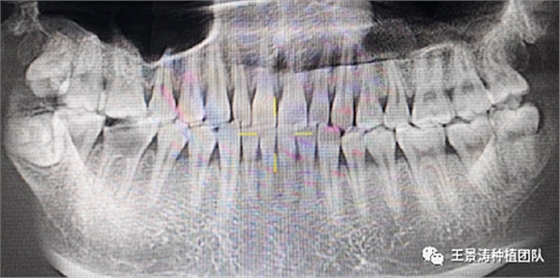

左側(cè)下頜第二磨牙及右側(cè)下頜第一磨牙同時(shí)即刻種植病例?;颊吣贻p女性,無系統(tǒng)性疾病。37及46殘冠及殘根,且46劈裂,無法冠修復(fù),必須拔除。37根尖慢性炎癥,大量肉芽組織存在,46根分叉較高,根分叉骨質(zhì)尚可。CBCT示:根尖骨質(zhì)至下牙槽神經(jīng)管距離可滿足種植體的初期穩(wěn)定性,遂考慮即刻種植,并在種植體周邊填入骨粉并覆蓋骨膜,雙側(cè)的種植體初期穩(wěn)定性相差無幾,但考慮到37根尖慢性炎癥較大,遂給予埋入式種植。